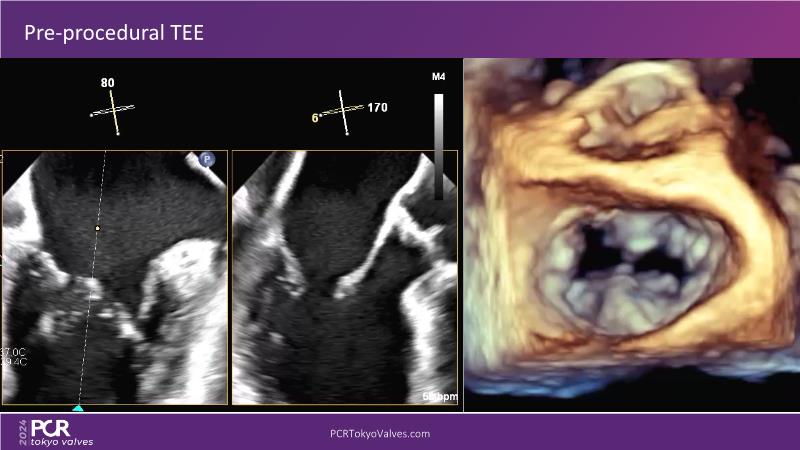

Watch this session to get an overview of a new TEER device, follow the step-by-step procedure related to initial experiences with this device for a Japanese patient with degenerative mitral regurgitation, learn about the latest data from RCT and registries, and follow discussions of challenging TEER cases!

- To learn procedural step-by-step of novel device